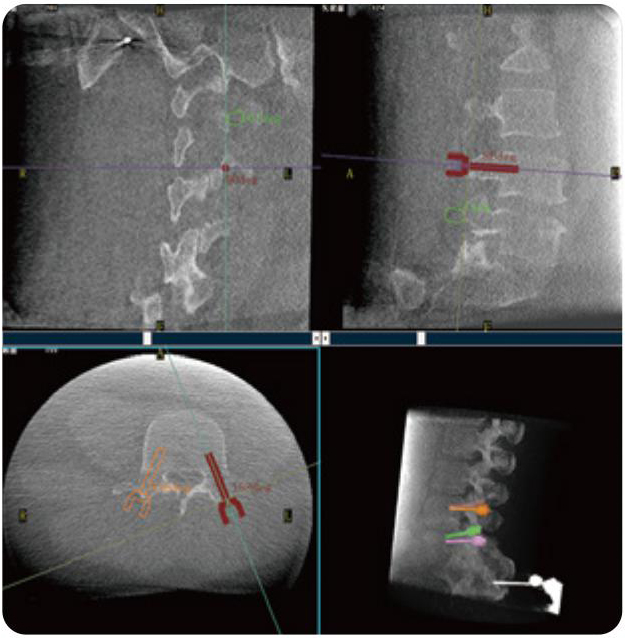

PL300B可應(yīng)用于多節(jié)段脊柱外科手術(shù),輔助醫(yī)生定位病灶部位,為脊柱外科手術(shù)(經(jīng)皮椎體成形術(shù)、椎弓根螺釘內(nèi)固定術(shù)等術(shù)式)提供術(shù)前手術(shù)流程規(guī)劃、入釘位置、角度可視化引導(dǎo),模擬仿真入釘輔助。